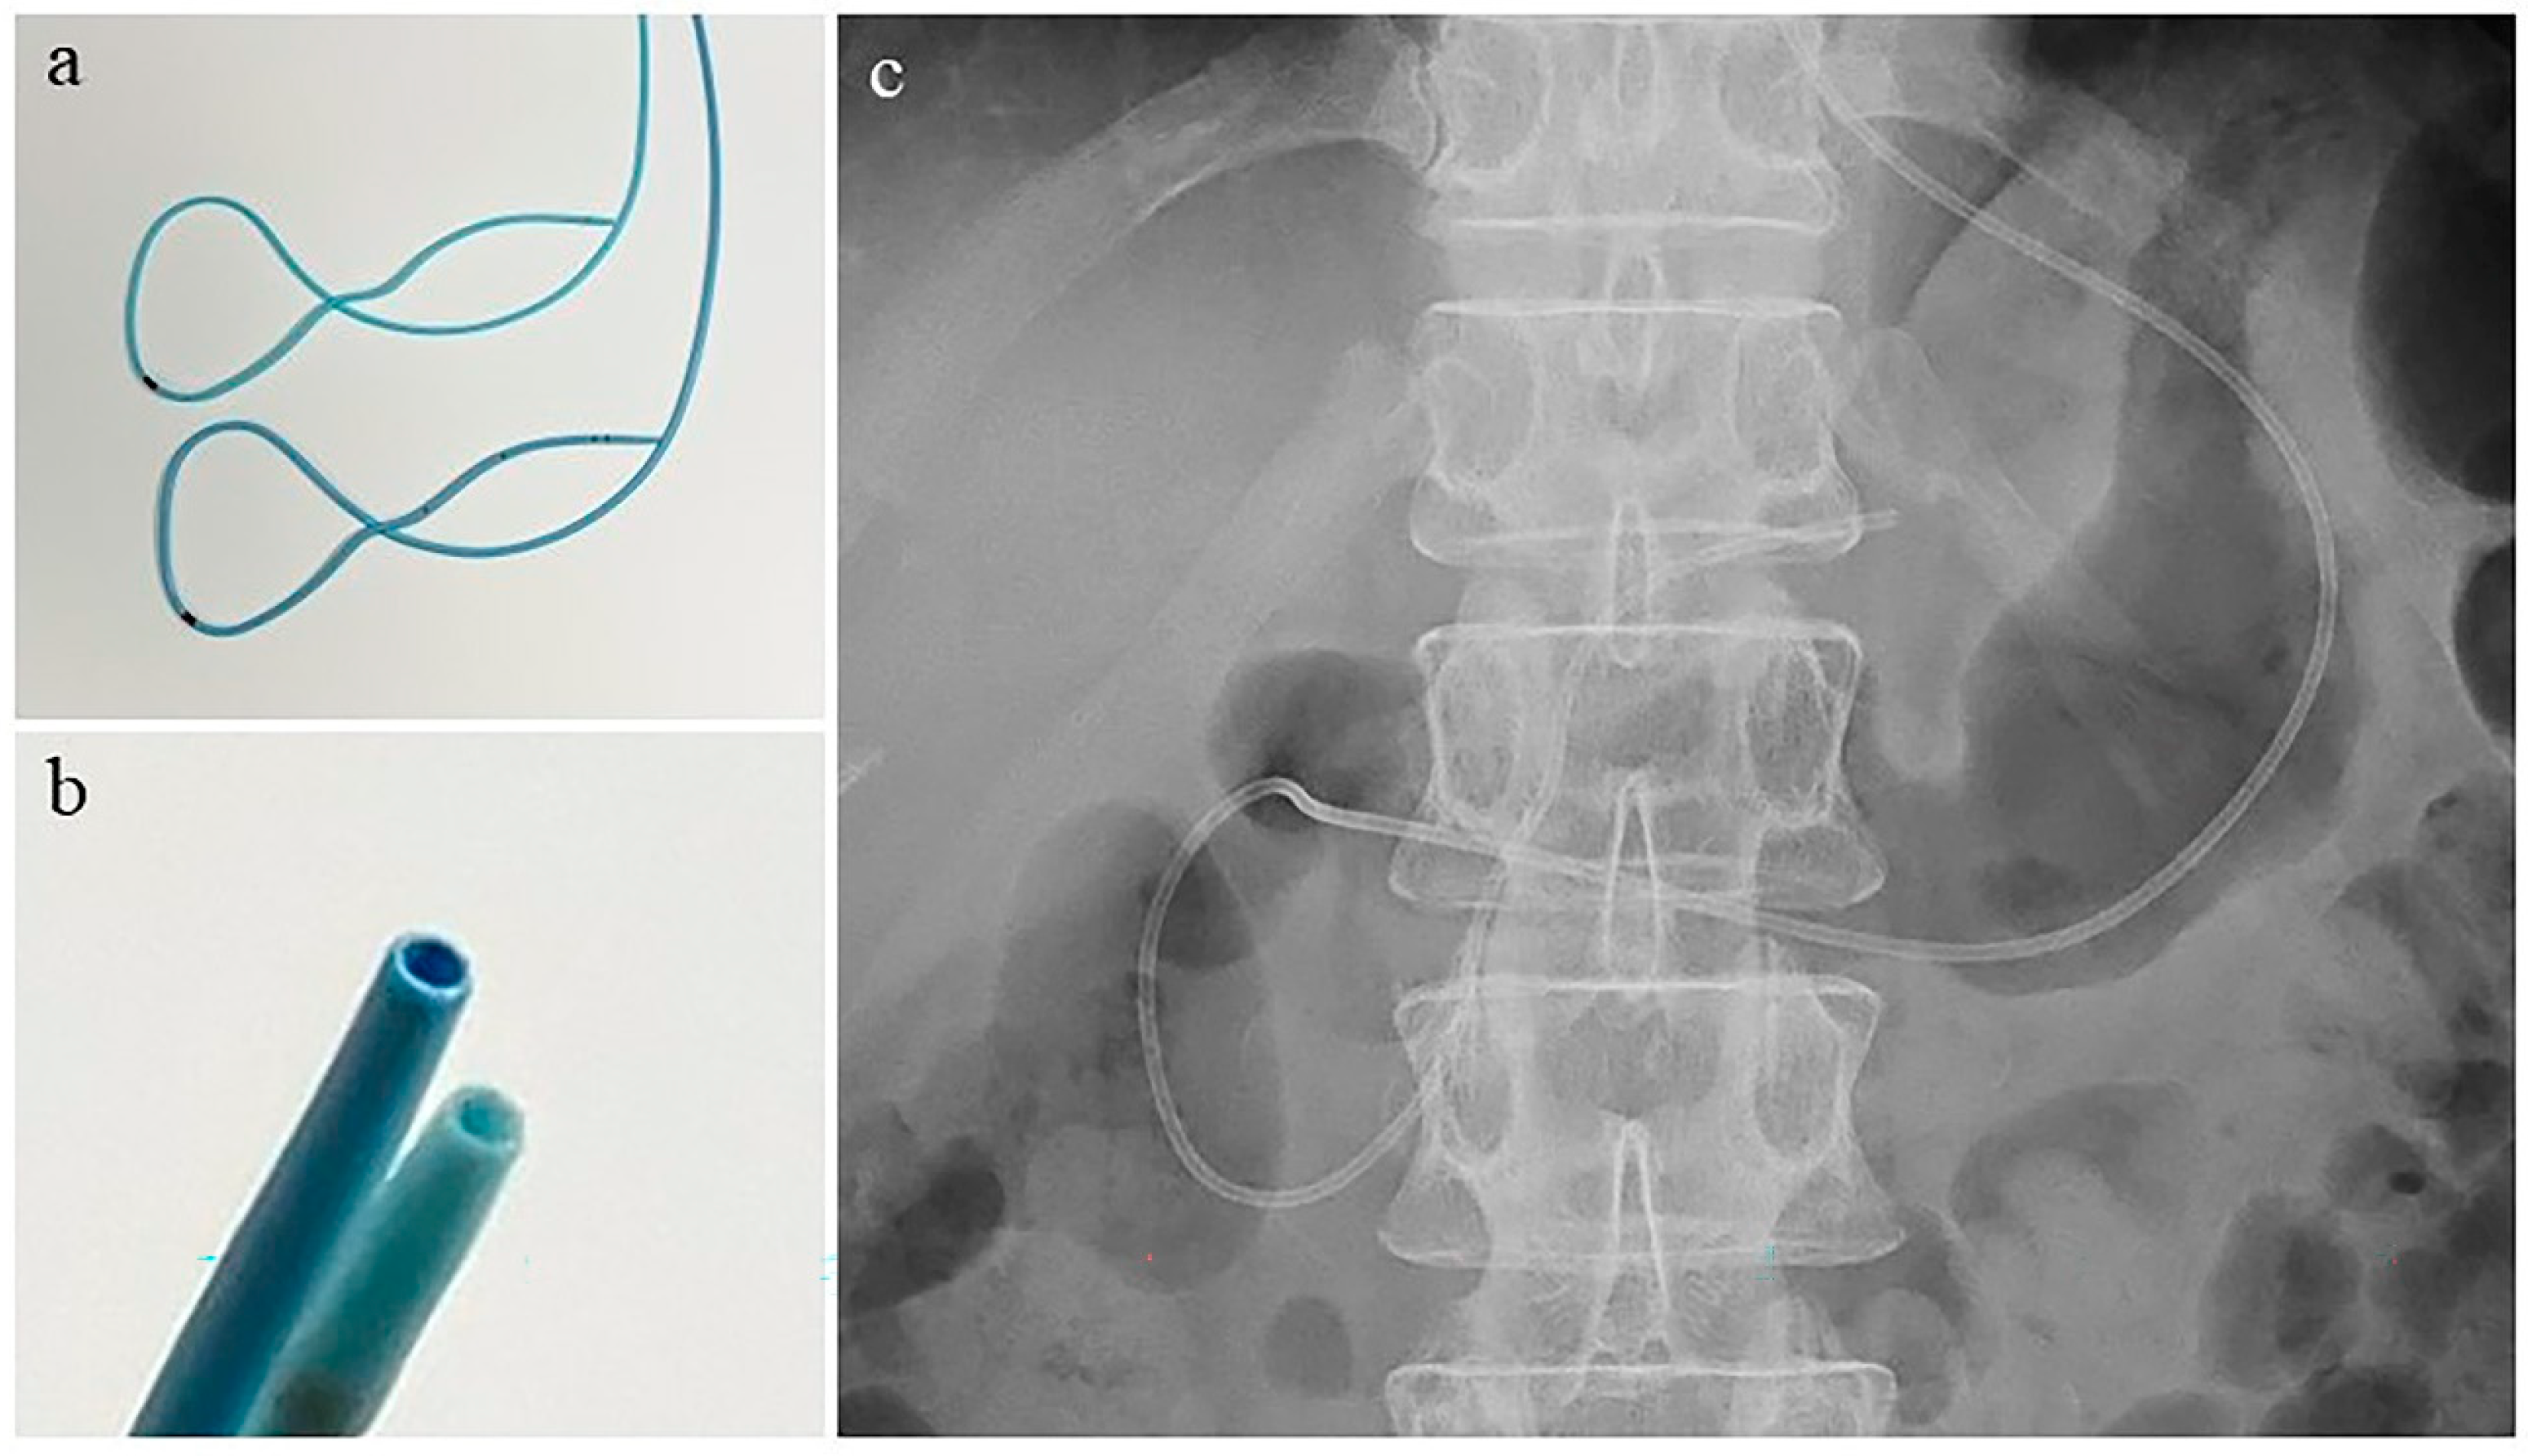

- Mouri, T.; Sasaki, T.; Serikawa, M.; Ishigaki, T.; Ishii, Y.; Shimizu, A.; Tsuboi, T.; Kurihara, K.; Tatsukawa, Y.; Miyaki, E.; et al. A comparison of 4-Fr with 5-Fr endoscopic nasopancreatic drainage catheters: A randomized, controlled trial. J. Gastroenterol. Hepatol. 2016, 31, 1783–1789. [Google Scholar] [CrossRef]

| Diameter of the ENPD catheter, n (%) | |

| 4-Fr | 62 (75.6%) |

| 5-Fr | 20 (24.4%) |